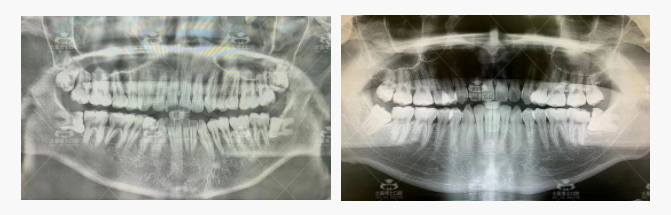

先来欣赏士嘉博士口腔医院患者口腔全景X片:

震惊!

大家看着X片里那些还没来得及拔掉的智齿,有没有人会觉得简直「负债累累」!